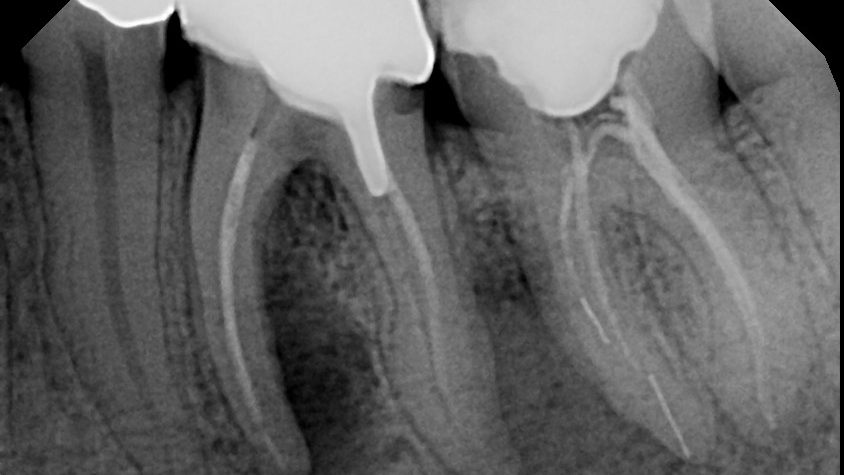

2. What is the clinical/radiographic presentation?

d. Is the bone loss vertical or horizontal, and what is the severity?